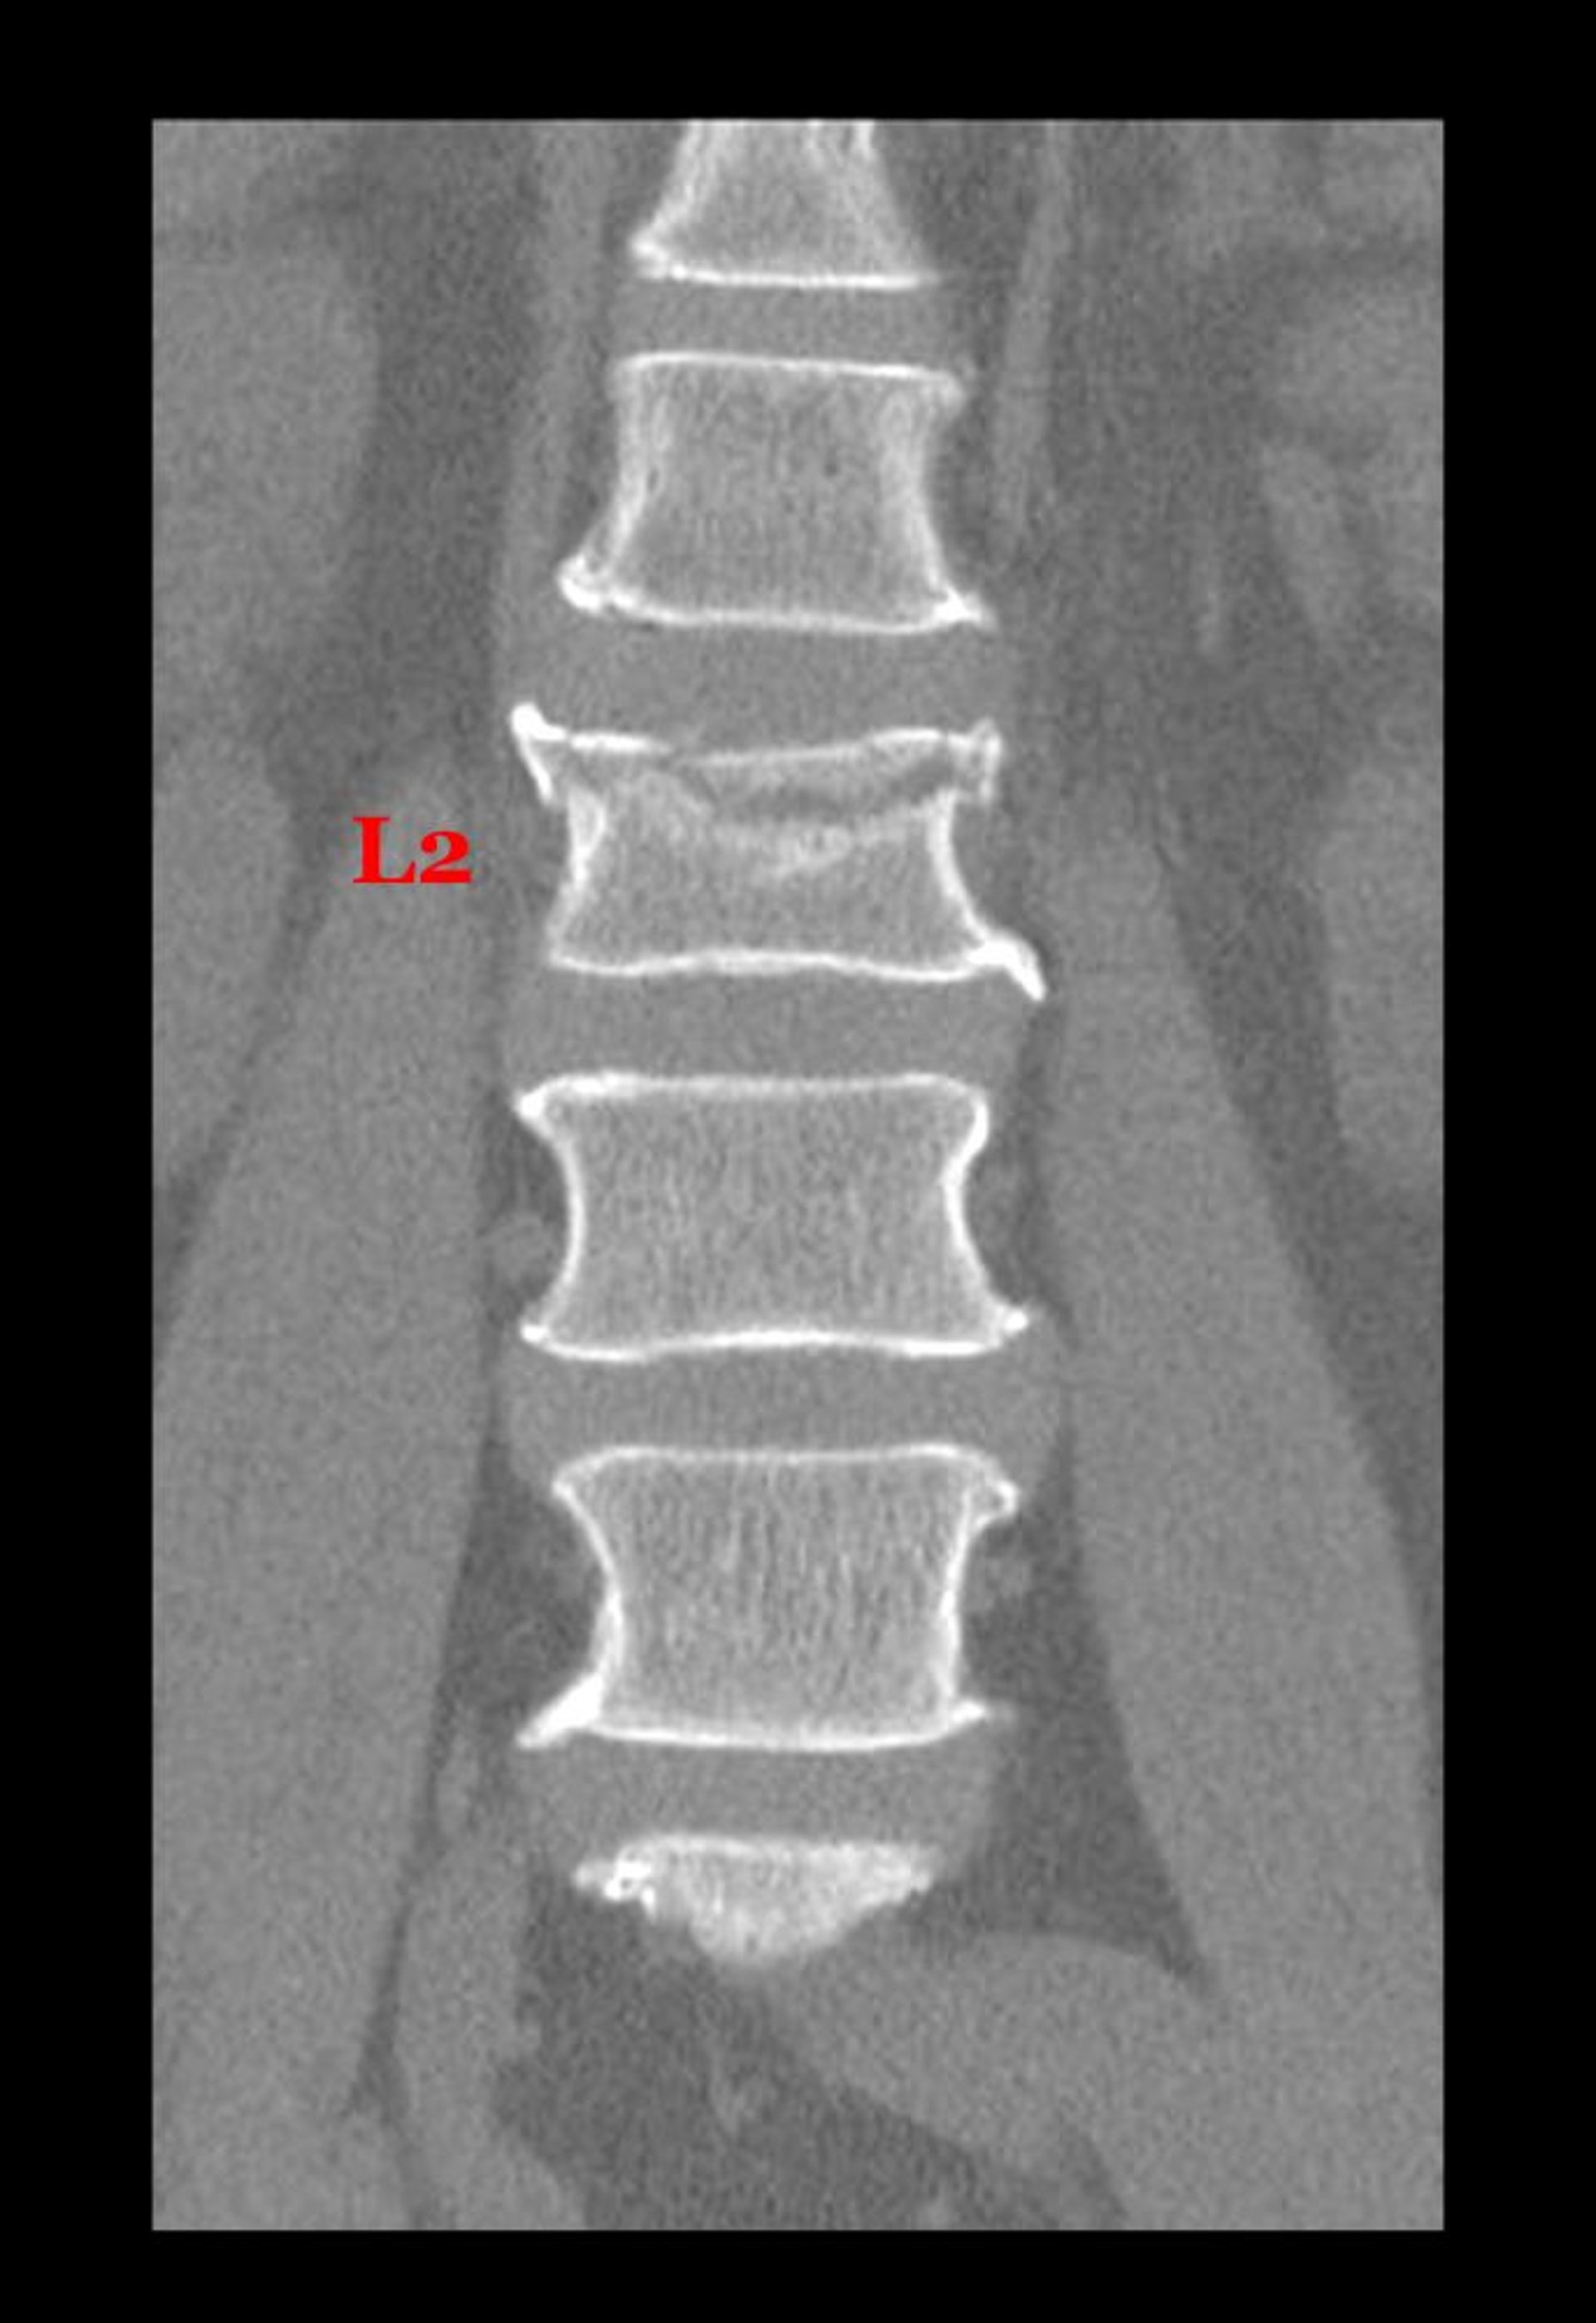

Kompressionsfraktur eines Lendenwirbelkörpers

Diese koronale (frontale) Ansicht von einem CT zeigt eine Fraktur durch die obere Seite des Körpers des 2. Lendenwirbels.